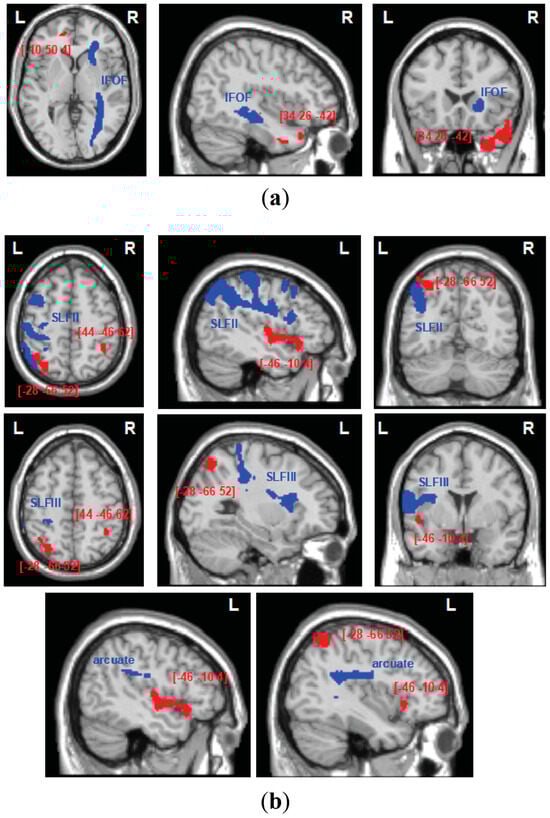

| Factor | Size (Voxels) | Z-Score | Coordinates (X, Y, Z) | Brain Structure |

|---|---|---|---|---|

| Automatic self-reference | ||||

| 1384 | 3.44 | 34 26 −42 | Right ITG 1 | |

| 50 | 3.41 | −10 50 4 | Left vmPFC 2 | |

| Control processing | ||||

| 405 | 3.93 | 44 −46 62 | Right IPL 3 | |

| 275 | 3.74 | −28 −66 52 | Left IPL 3 | |

| 343 | 3.39 | −46 −10 4 | Left AIC 4 | |